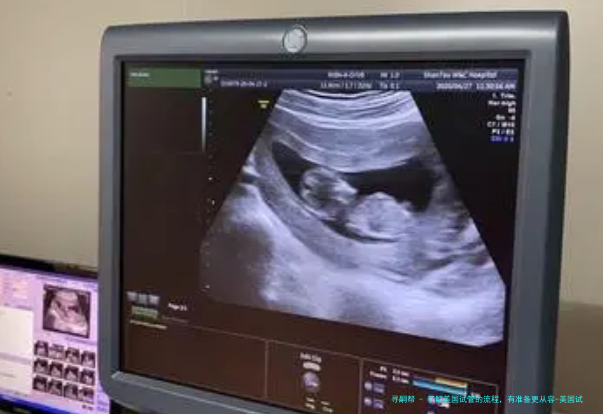

2、B超检查

第二次看诊的时间诊所护师会帮客人确认,按照护士的要求,定期进行B超检查、抽血检查以及卵泡监测,卵泡的监测一般在监测4-5次就能安排助孕。

该流程重点注意:屡屡监测卵泡必需保障进行了B超、血液检查以及确认可了下一次检查日期后方可返回寓所。尽可能每日同一时间使用药物。